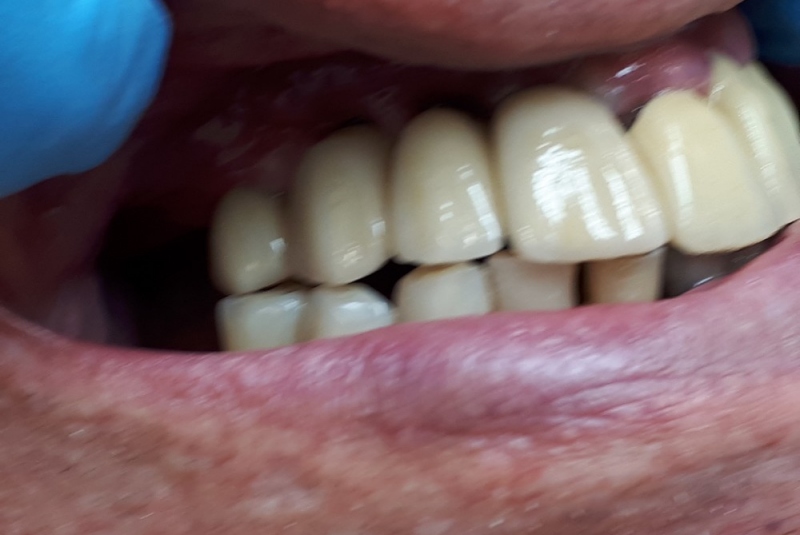

- Implantológia:

1. nadstavba kosti augmentačnými materiálmi (umelé kostné tkanivo, sinus lift a pod.)

2. implantológia, vrátane 3D - dentálneho CT